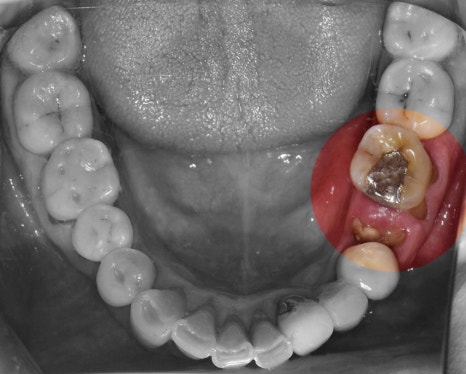

뼈와 다 아물게 되면, 오른쪽 사진에서

보실 수 있는 것 처럼 지르코니아 크라운이

연결이 되면 모든 시술은 끝나게 됩니다.

이 분의 경우에는, 만 65세가 넘으셨기 때문에

보험 임플란트 적용이 가능했었습니다.

따라서, 상악에는 지르코니아 크라운이 아닌

PFM 크라운으로 셋팅을 해드렸으며

하악에만 지르코니아 크라운이 연결되었습니다.